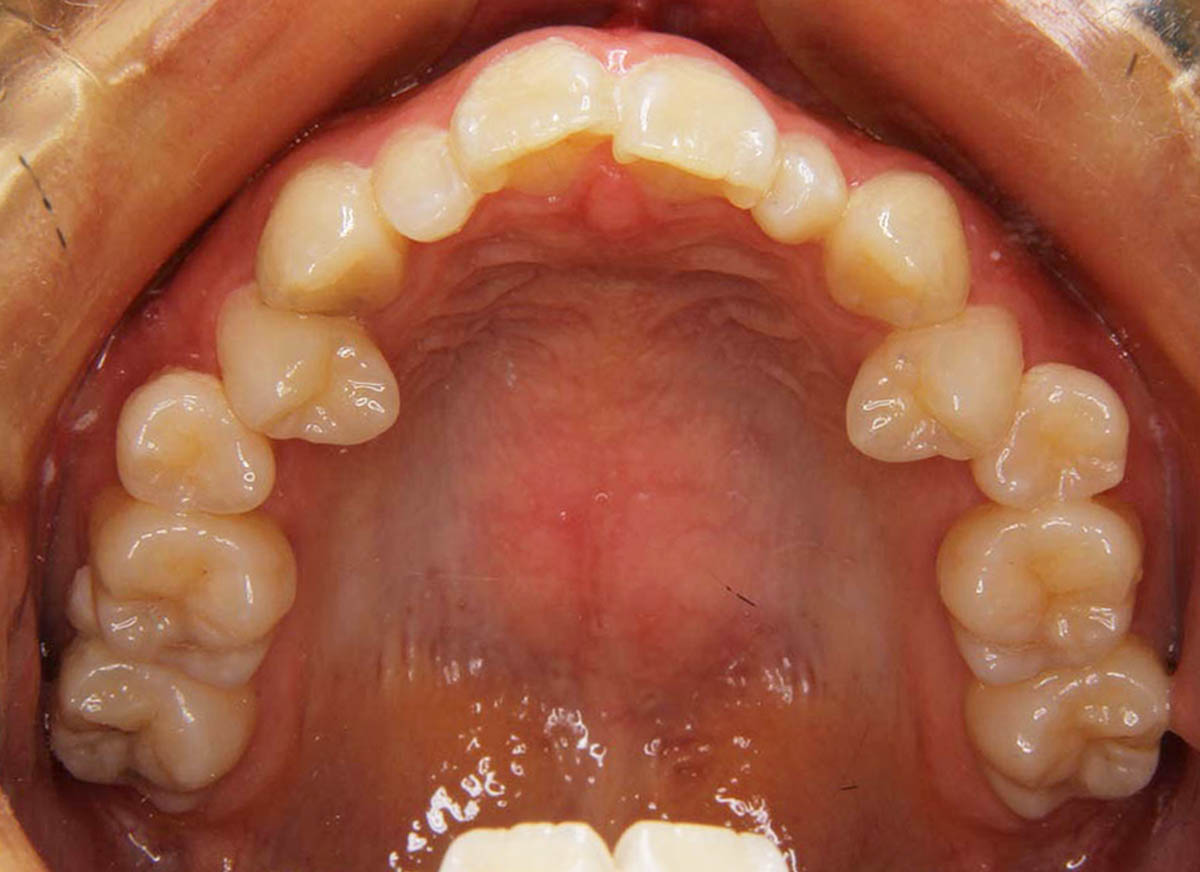

叢生(デコボコ)症例

●主訴

歯のデコボコが気になる

●診断

AngleⅠ級・前歯部叢生

●治療に用いた主な装置

上下顎にマルチブラケット(表側装置)

●抜歯部位

上下左右第一小臼歯4本

●治療期間

2年6ヶ月

●治療費用

約92万円(ともに税込、調整費、保定費まで含む総額制)

●付記

デコボコがきつかったので抜歯症例となりました。

リスクとして、

①歯根吸収…今回は全くありませんでした。

②カリエス(むし歯)…今回は治療途中でむし歯治療を行いました。

③あともどり…保定装置の装着をしっかりしていただいています。